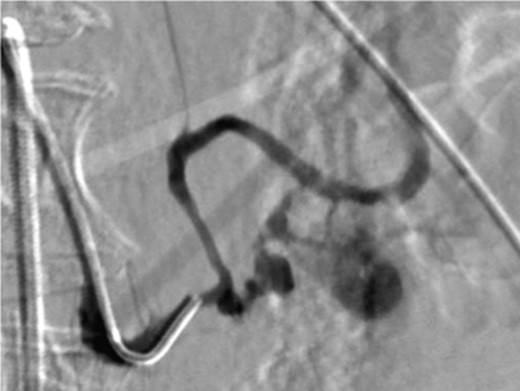

A frail 77-year-old multiparous Caucasian female with a history of aspirin and naproxen use, presented to an outside hospital with epigastric pain and an episode of hematemesis. She had no prior history of peptic ulcer disease, alcoholism or pancreatitis. The patient was hemodynamically stable with an acute anemia (hemoglobin of 7.7 g/dl), which prompted transfusion of 2 units of PRBC and transfer to a tertiary care facility. Upon transfer, she underwent an emergent upper endoscopy, which revealed a large amount of blood with clots in the lumen of the stomach. However, sufficient suctioning of the large intra-gastric clots was not possible; hence, an underlying etiology was not obtainable. The patient subsequently underwent a diagnostic angiography, which revealed a 4 cm mid-SA pseudoaneurysm with active contrast extravasation into the stomach which can be seen in Figs 1 and 2. The radiologist decided to perform a transcatheter arterial coil embolization of the artery to halt the active bleeding. A post procedure angiography revealed no further contrast extravasation. A planned upper endoscopy was repeated the following day that revealed some residual clotted blood in the stomach, no active bleeding and a deep 4 cm gastric ulcer. Due to the high risk of re-bleeding, the patient was optimized physiologically and consented and prepared for exploration. Intraoperatively we observed that the SA pseudoaneurysm was densely adherent to the posterior wall of the stomach, and coursing through an inflamed distal pancreas. We decided to proceed with an en bloc resection of SA pseudoaneurysm, distal pancreatectomy, partial gastrectomy and splenectomy. After the celiac axis was surgically defined, proximal and distal SA controls were obtained and a circumferential posterior gastrotomy was made. There was a visible posterior gastric mucosa to splenic arterial fistula, with the radiologically inserted embolic coils clearly visible. This can be seen in surgical specimen (Figs 3 and 4). Once the stomach was reflected, the splenic vessels and the pancreas were divided and the specimen removed. The pathology reports indicated active gastritis with transmural ulceration into the splenic artery (SA) and adjacent pancreatic tissue. No malignant cells were identified in the gastric or pancreatic tissue and the SA was not aneurysmal (Fig. 5). During the postoperative period, the patient had an uncomplicated recovery and was discharged on day 5.

Surgical specimen of en bloc partial gastrectomy, distal pancreatectomy and splenectomy.

Surgical specimen of en bloc partial gastrectomy, distal pancreatectomy and splenectomy. Embolic coils visible in arterial lumen.